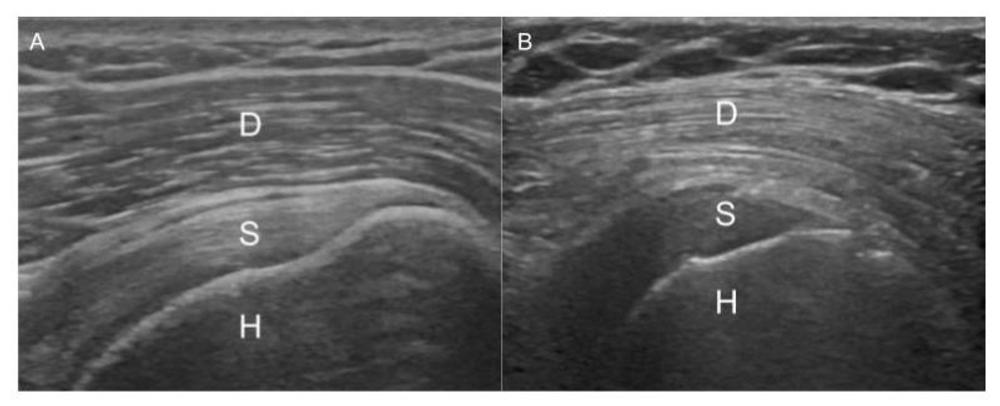

Figure 1. Images of the shoulder showing reversal of the rotator cuff to deltoid gradient. Image A displays the normal gradient of the deltoid muscle to the supraspinatus tendon. Image B shows reversal of the normal gradient in a type 2 diabetic patient. D: Deltoid, S: Supraspinatus, H: Humerus

High-res (TIF) version